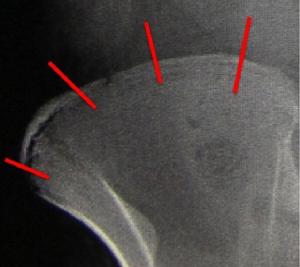

以及對於患者生長潛力的評價Risser征等。Risser征是通過雙側髂骨表面骨骺閉合的情況,評價患者的生長潛能。(圖1-4)